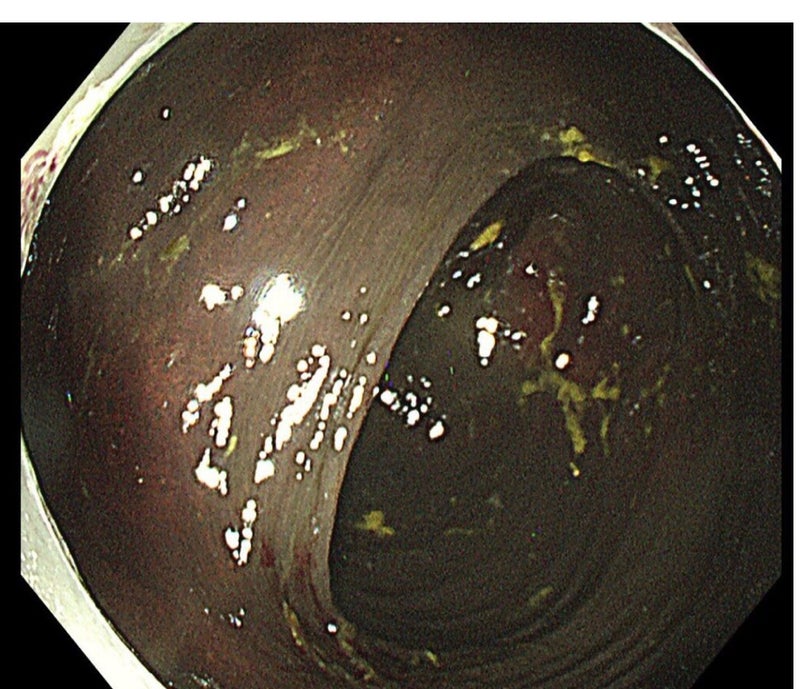

下剤を飲み続けた腸は真っ黒。

大腸メラノーシスでも大腸ガンになりやすいわけではない。

大腸の筋層の神経細胞が減少し腸の動きが鈍くなり、

便秘の症状が悪化していきます

下剤が効きにくくなる。

色素沈着はアントラキノン系下剤にはセンナ、アロエ、大黄、カスカラ、

キャンドルブッシュ。

辞めて1年程で色素沈着と腸管の弛緩も改善

↓は正常になるまで2年